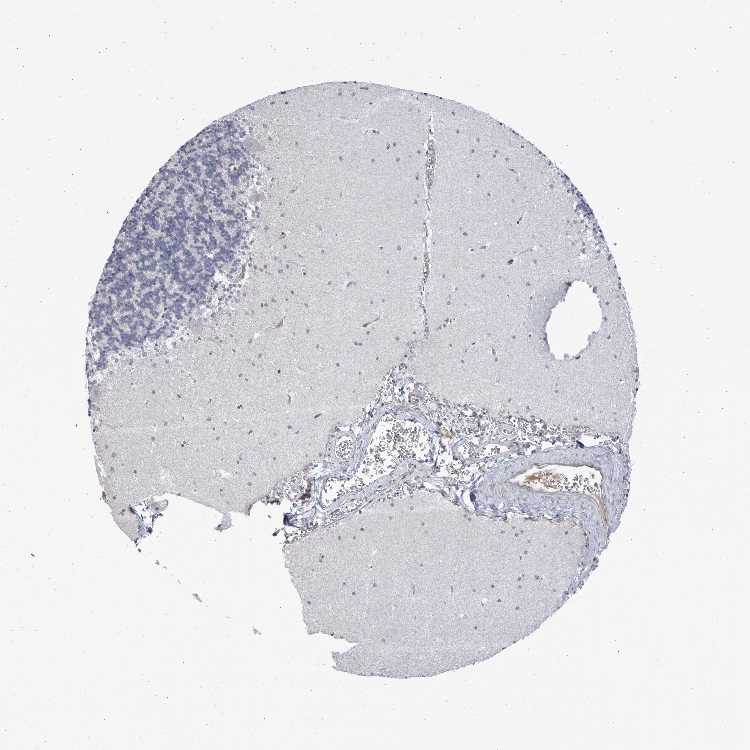

CEREBELLUM - Antibody stainingi

Antibody staining in the annotated cell types in the current human tissue is reported as not detected, low, medium, or high, based on conventional immunohistochemistry profiling in selected tissues. This score is based on the combination of the staining intensity and fraction of stained cells.

Each image is clickable and will lead to virtual microscopy that enables deeper exploration of all samples and also displays staining intensity scores, fraction scores and subcellular localization as well as patient and tissue information for each sample.

Antibody HPA026436Antibody HPA026451Antibody HPA026501

Purkinje cells HighMediumNot detected

Cells in granular layer HighMediumNot detected

Cells in molecular layer HighMediumNot detected